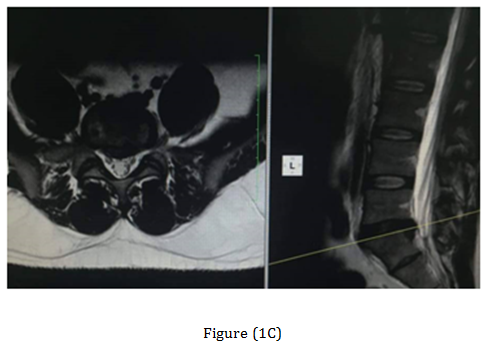

The post-operative Antero-posterior, lateral radiographs and dynamic views were used to assess the fusion mass at each level. The plain radiographs were obtained at 3 months, 6 months, 12 months, 18 months and 24 months to assess fusion status. Solid arthrodesis of the interbody space was confirmed by the presence of continuous bridging bone observed on the lateral radiographs, absence of lucencies around the cages, no cage migration or collapse and absence of halo around the screws. By Using this criteria, solid fusion was achieved in 18 patients (90%), whereas pseudarthrosis was documented in two patients. Low back and leg pain were completely resolved in 18 patients (90%) according to VAS (Table 1). All patients were rated minimal disability according to ODI (Table 2). The radiological outcome (Figure 1) showed solid fusion was achieved in 18 patients (90%), whereas pseudarthrosis was documented in two patients.

Figure 1 Case 3 with L.D.P L5-S1. (A) Preoperative radiograph anteroposterior and lateral views. (B) Preoperative MRI. (C) Post-operative radiographs anteroposterior and lateral views. (D) At the 18-months follow up anteroposterior and lateral views radiograph.